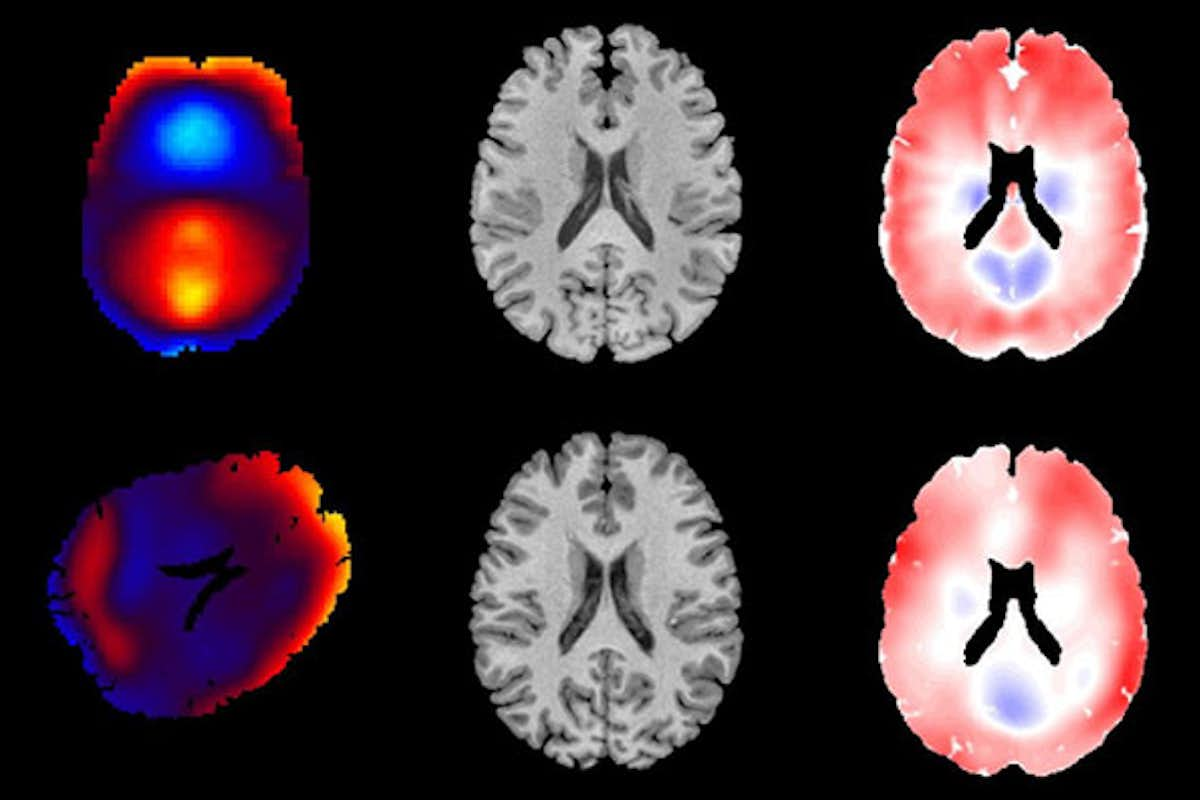

Jordan Escarcega in Philip Bayly's lab studied deformation of brain tissue using MRE (top row) and tagged MRI (bottom row). These measurements will be useful to evaluate and improve computer models of brain biomechanics, which can then inform the design of protective equipment and reducing the societal burden of traumatic brain injury. (Credit: Jordan Escarcega)

In the first case, the human volunteers’ heads were resting in a cradle while undergoing tagged MRI imaging. The volunteers were asked to gently rotate their head side to side — as if shaking their head “no” — until the cradle stopped the movement, which created the impulse response. To see the impulse response of the brain in tagged MRI, a grid of lines is superimposed over the MR image of the moving brain to see the deformation of the brain when the volunteer’s head was stopped by the cradle.

In the second experiment, light sound pressure generated by a speaker was applied to the volunteers’ heads to generate a harmonic response. Brain motion was measured using MR elastography, or MRE, a noninvasive technique that combines MRI images with low-frequency vibrations to create a visual map that shows information on body tissues.

“In the harmonic response, you’re getting a single sustained wave pattern, whereas in an impulse response, you’re getting a complex behavior that consists of the responses to multiple  frequencies added together,” said Escarcega, who first came to Washington University as part of the Washington University Summer Engineering Fellowship Program (WUSEF), then returned to earn a doctorate. “Using the tagged MRI, we are able to break down the impulse response into the most dominant components and compare those to the harmonic waveforms that we excite in MRE.”

“Every human brain is different – it might as well be like your fingerprint,” Escarcega said. “But what we found was the physical patterns of deformation produced by MR elastography are extremely similar to the patterns you see from when people bump their heads.”

Tagged MRI is more difficult to perform than MRE because it requires participants to move their heads many times. Bayly and Escarcega said that MRE, which is simpler and more widely available, can be used to show the brain’s response to head impact. This result has important practical implications, they said.

“Using MRE, we can quantitatively measure patterns of brain deformation that are expected in response to head impact, but without the longer experiments and added difficulty of tagged MRI,” Bayly said. “These measurements will be useful to evaluate and improve computer models of brain biomechanics, which can then inform the design of protective equipment and reducing the societal burden of traumatic brain injury.”